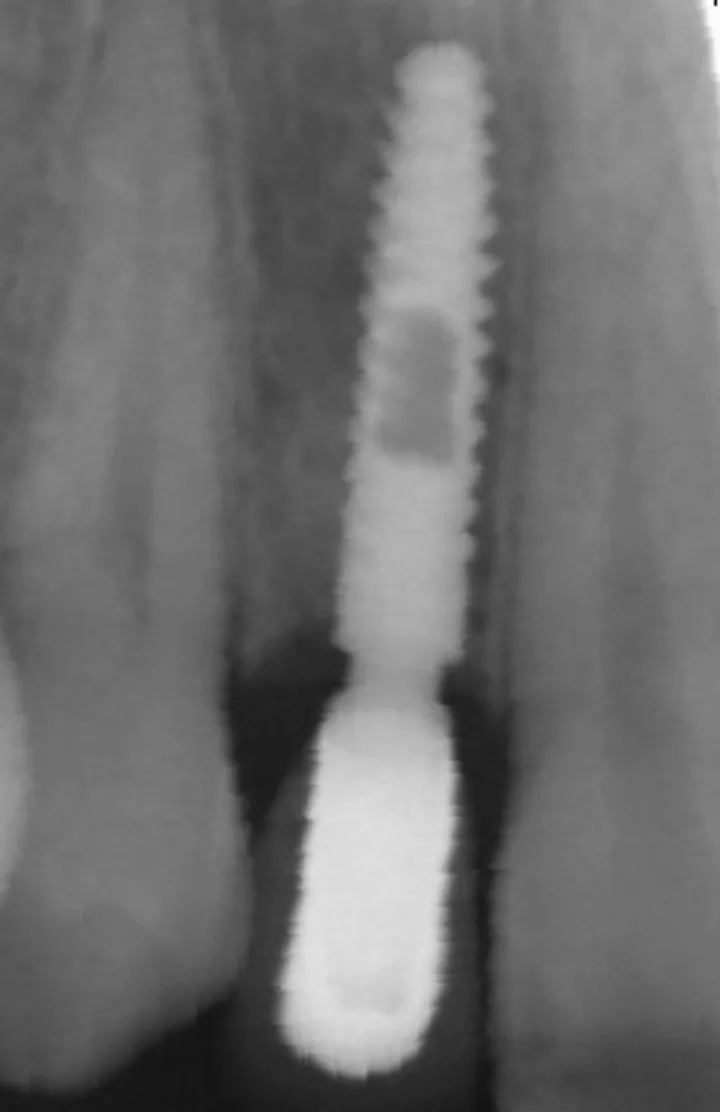

由一名独立评估人员使用 Kinovea 软件对骨组织水平进行了 X 线测量,测量结果用种植体实际长度进行校准(图 2)。研究开始时测量的骨组织水平(首次种植术时骨水平)与种植术后 1 年时测量的骨组织水平之差即为骨吸收。

平均骨组织水平经近中和远中水平值计算得出。

图2:术后 1 年近、远中骨组织水平测量值。